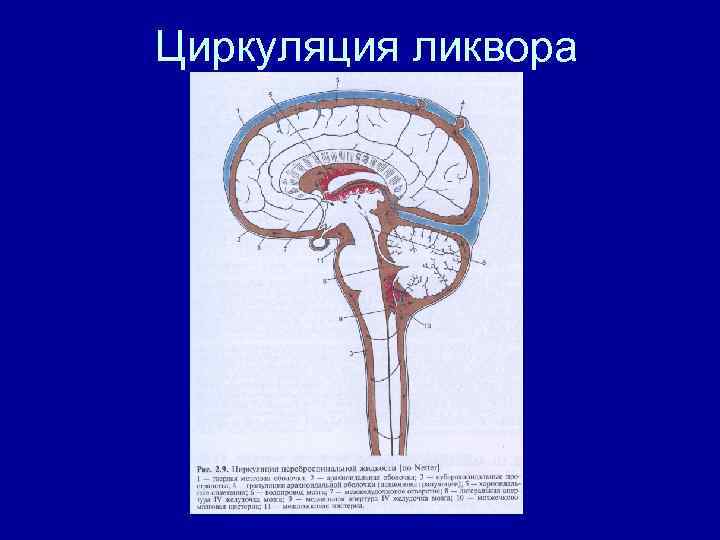

Циркуляция ликвора

Циркуляция ликвора